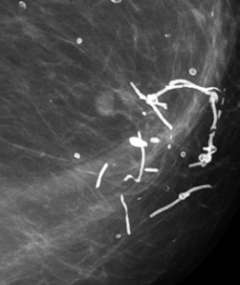

Distribution of Calcifications

From left to right: linear, grouped, segmental, regional, and diffuse.